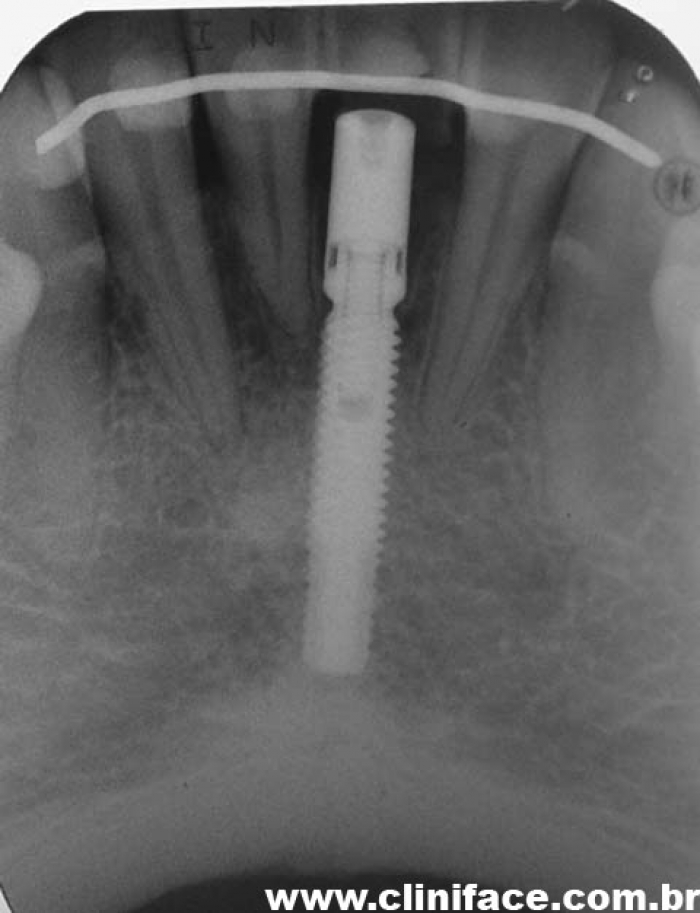

Imagens finais do caso terminado em fevereiro de 2010, com prótese em porcelana sobre implante

Rx final